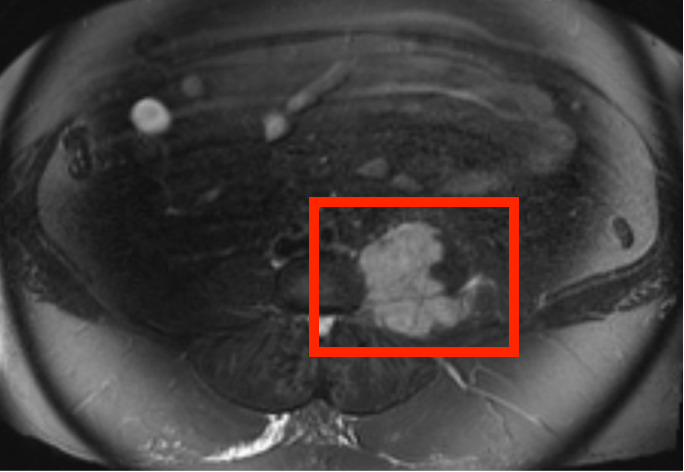

Additionally, the patient described the pain as continuous and achy, with no associated numbness or tingling. Interestingly, the patient denied any constitutional symptoms such as fevers, weight loss, or night sweats that would have raised a higher degree of suspicion for a recurrence of her previous cancer. This pain was thought to be chronic pain as it was first noted in her chart 4 months prior to her fall in the bathtub. Prior lumbosacral X-rays showed no acute abnormalities in the lumbosacral spine but demonstrated joint narrowing at L3-L4, prompting a magnetic resonance imaging (MRI) of the lumbar spine for suspected L3 radiculopathy. The MRI revealed a 6.7 cm left lumbosacral paravertebral mass with bone invasion of the L5 and S1 vertebral bodies and encasement of the L3-L5 nerve roots. [Figures 1 and 2]